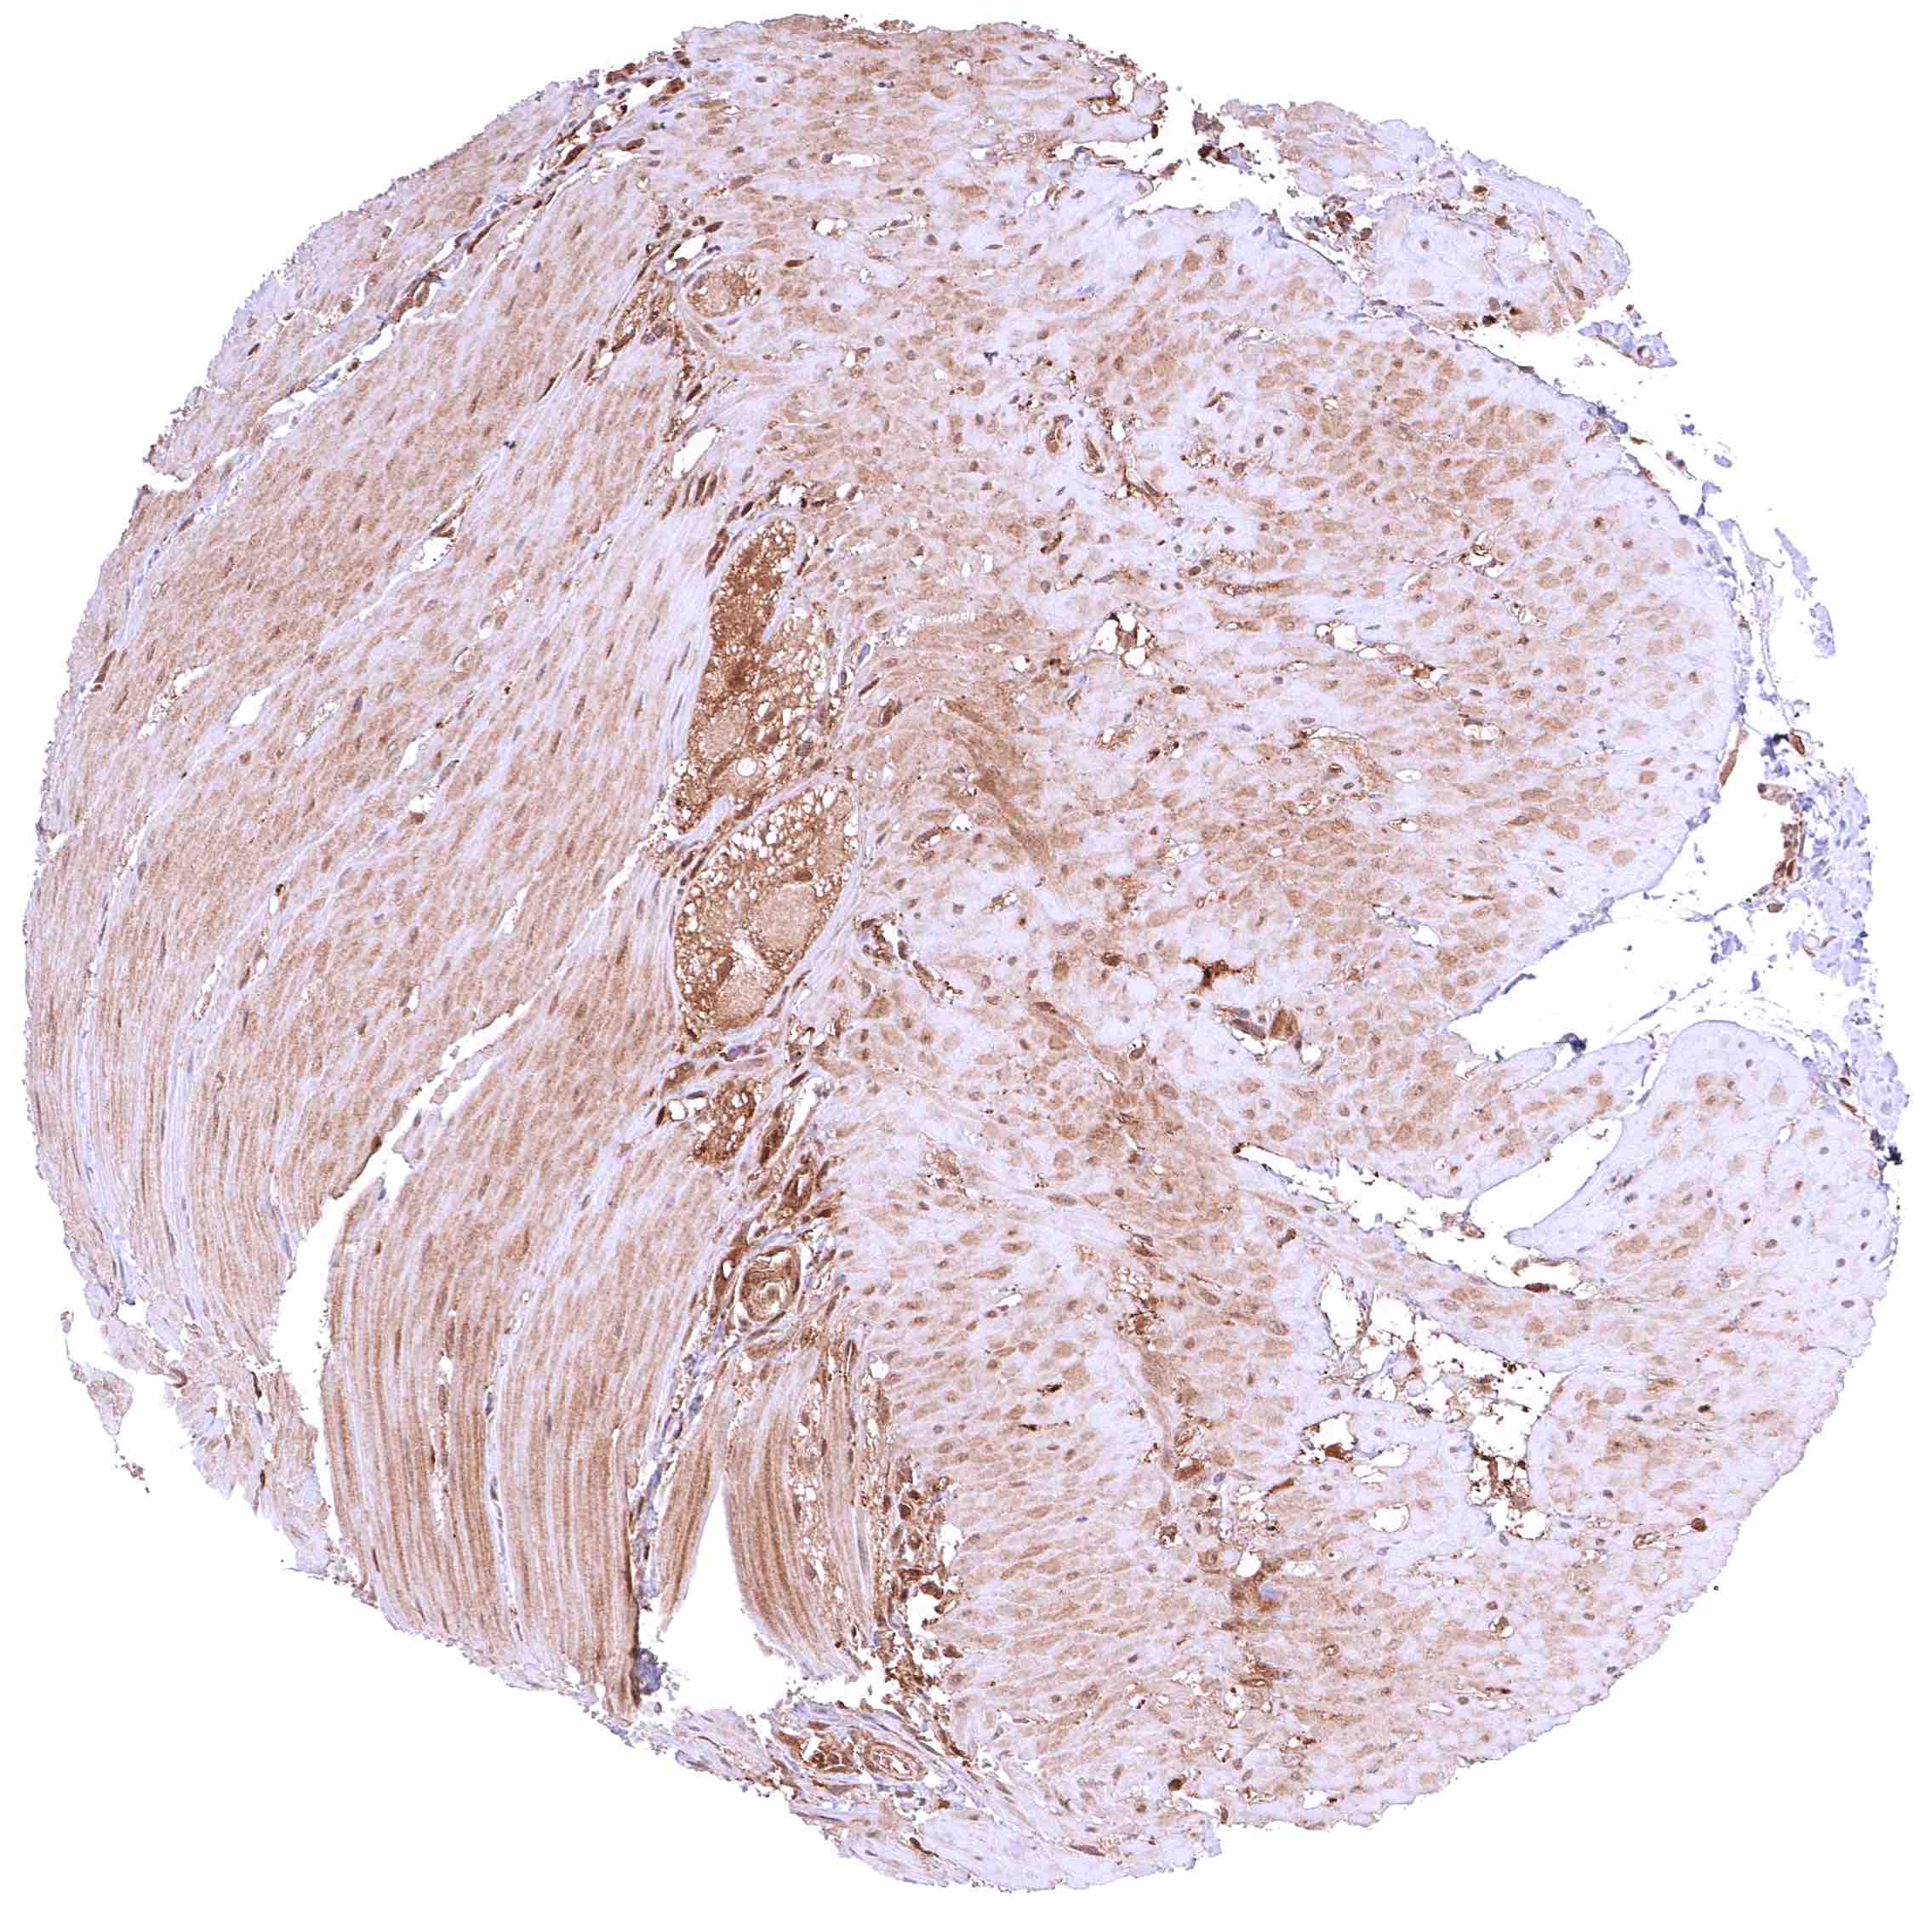

Esophagus, muscular wall – Faint cytoplasmic GSTP1 positivity of smooth muscle cells.

Esophagus, squamous epithelium – Strong cytoplasmic and nuclear GSTP1 positivity of squamous epithelial cells. Staining intensity is highest in the basal and suprabasal cell layers and decreases slightly towards the surface